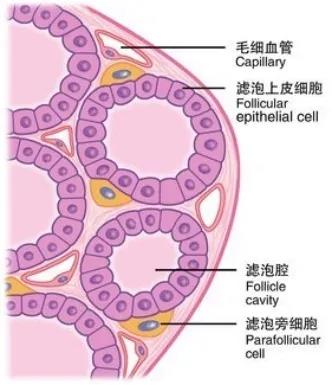

懒癌会复发吗? 甲状腺癌是最为常见的一种内分泌恶性肿瘤,近10年来,其发病率在全球持续快速上涨。约95%的甲状腺癌为分化型甲状腺癌 ( differentiated thyroid cancer,DTC) ,也就是俗称的“懒癌”,主要包括甲状腺乳头状癌( papillary thyroid carcinoma,PTC) ,甲状腺滤泡状癌( follicular thyroid carcinoma,FTC) 和嗜酸细胞癌( Hürthle cell carcinoma,HCC) 。 分化型甲状腺癌(DTC)的长期预后非常好,在10年随访中,成人DTC患者的生存率为92-98%。然而,5%-20%的患者出现局部或区域复发,复发时间从6个月至数十年不等,10-15%的患者继续发展为远处转移。甲状腺床和颈部淋巴结是DTC患者最常见的局部或区域复发部位,而远处转移主要见于肺和骨骼。